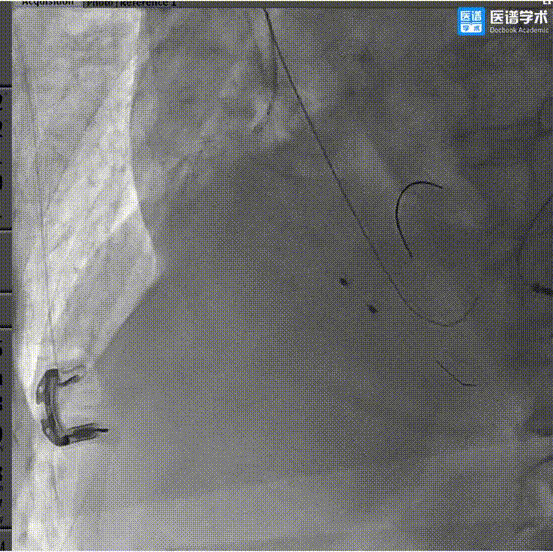

7、经6F JR3.5指引导管,送入3.5×28mm支架至RCA近段,预备行烟囱支架术;

9、超声评估示平均跨瓣压差约5mmHg、微量瓣周漏,造影未见明显反流影;

10、猪尾导管测压显示,平均跨瓣压差约2mmHg,造影示瓣膜定位良好、开放良好,极少量瓣周漏,患者血流动力学指标稳定,血压约101/55mmHg,人工瓣膜开口面积2.06cm2,标志手术成功。